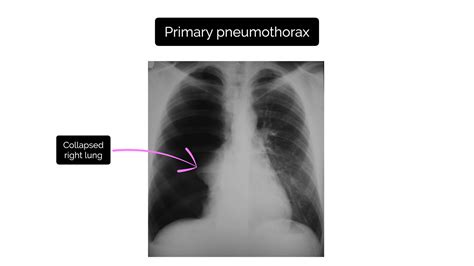

• Case 1: Spontaneous Pneumothorax: A 25-year-old male presented with sudden onset of chest pain and shortness of breath. An X Ray Of Pneumothorax revealed a small pneumothorax on the right side. The patient was observed in the hospital for 24 hours and discharged with instructions to avoid strenuous activity. Follow-up X-rays showed resolution of the pneumothorax.

• Case 2: Traumatic Pneumothorax: A 40-year-old female was involved in a car accident and sustained multiple injuries, including a pneumothorax on the left side. An X Ray Of Pneumothorax confirmed the diagnosis, and a chest tube was inserted to drain the air from the pleural space. The patient recovered fully after a week in the hospital.

These cases highlight the effectiveness of an X Ray Of Pneumothorax in diagnosing and managing pneumothorax, regardless of the underlying cause.